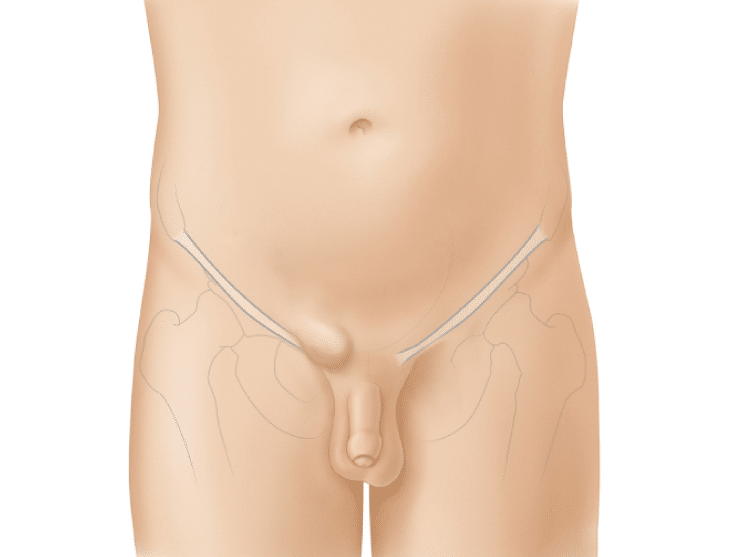

Hernia inguinal

Dolor o incomodidad en la ingle, especialmente cuando te inclinas, toses o levantas peso.